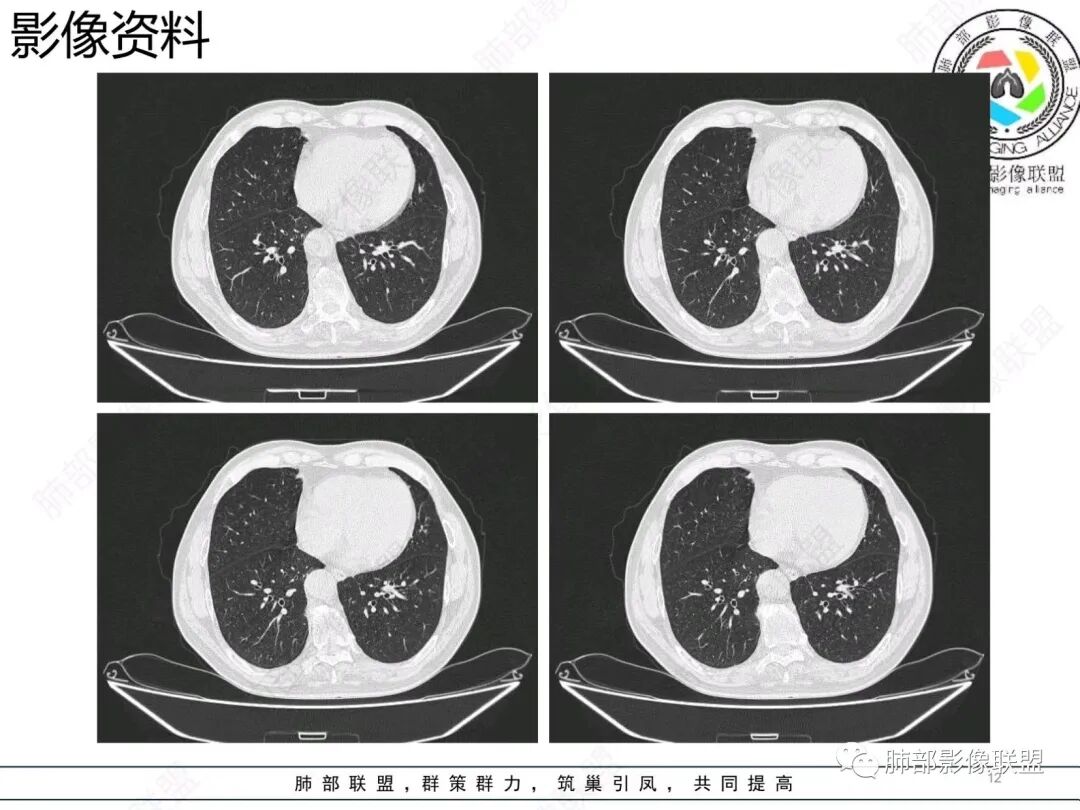

老年男性,右肺下叶混合磨玻璃密度结节,可见血管弯征,首先考虑肺腺癌。

右肺下叶背段不规则结节,边界欠清,可见少许晕征,另见胸膜凹陷征及血管弯,考虑腺癌,鉴别隐球菌。

老年男性,右肺下叶胸膜下结节,边缘见清晰磨玻璃密度影及少许索条,支气管进入后截断,周围血管弯,考虑腺癌,鉴别隐球菌

右肺下叶胸膜下混合密度结节,分叶、毛刺,磨玻璃边界尚清晰,血管集束,支气管进入阻断,考虑腺癌

右肺下叶背段胸膜下肿块,边缘不规则,分叶,毛刺,有磨玻璃,边界清,近肺门侧见血管聚集,支气管进入后闭塞,右肺下叶肺静脉牵拉扭曲。诊断,支持腺癌

右肺下叶胸膜下结节,边界清楚毛玻璃,有分叶、毛刺、血管集束及胸膜增厚,考虑肉芽肿性病变,鉴别于腺癌

右肺下叶后基底段胸膜下斑块影,边缘清楚,有平直和膨隆特点,周围清楚GGO,较模糊(似清非清,邻近见多发纯GGO结节,以肺腺泡分布,主体病灶与胸膜平行,收缩力弱,边缘见支气管充气征,首诊断炎性肉芽肿,抗炎治疗和查下隐球荚膜抗原两方面进行,另取旧片对比,与粘液腺Ca鉴别,最后经皮肺穿刺病理诊断!

结节型粘液腺癌,具有血管弯,支气管截断,磨玻璃边界清楚等恶性征象,同时磨玻璃内部较糊,似清非清,不符合普通腺癌附壁生长特点,更像局限的粘液成分。收缩力不强,胸膜局部微积液,内部小空洞(考虑局部粘液排除形成),所以考虑结节型粘液腺癌。

区别1:结节期(影像说结节型)粘液腺癌,粘液成分还大多数局限于粘液腺癌细胞的胞浆中,没有飘出去,所以粘液密度不明显,周围的磨玻璃成分大多数还是分散于肺泡壁上的粘液腺癌细胞,所以边界相对较清楚(时间越晚,飘出去的粘液越多,边界就会越不清楚了),因为胞浆中的粘液成分显得较糊,有点似清非清。而普通腺癌附壁生长的腺癌细胞胞浆中没有粘液,所以非常清楚。

区别2:粘液腺癌的MGGN收缩力不强,普通腺癌的MGGN收缩力明显。